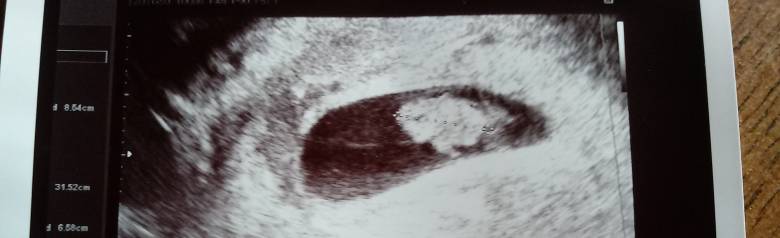

No więc termin tak jak sobie wyliczyłam - 7 lipca. CRL 19mm, piękne serduszko . Następna wizyta w Sylwestra![]()